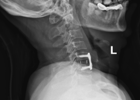

近期,长期受到颈肩部及右上肢疼痛、麻木困扰的郭阿姨,在广东省人民医院(下称“省人医”)帮扶及我院骨科的共同努力下,经过全面评估,确诊为神经根型颈椎病,并成功实施了颈椎前路椎间盘摘除术。术后,她的症状明显改善,不久便恢复了往日的活力。 术前MR 术后MR 术后DR 在现代快节奏的生活中,颈椎问题已经成...2024-07-12